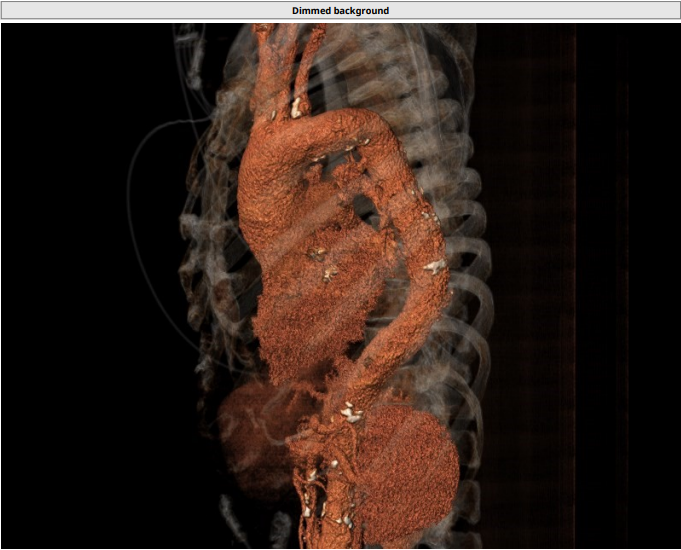

CT 报告

主动脉根部:

Annulus:23.3 mm,LVOT:21.9 mm,STJ:30.8 mm,Asc.AO:43.5 mm

LCA:13.2 mm,RCC:14.0 mm

瓣环及左室流出道呈开放式结构

TYPE1 二叶瓣,钙化集中无冠窦瓣叶侧

升主动脉增宽,最宽处为 47.1 mm(55.7 mm)

左右冠高度合适

心肌增厚,心室小

主动脉弓部走行尚可,降部有折角;髂股动脉有钙化分布,左右股动脉走行迂曲

TYPE1 型二叶瓣,重度钙化,钙化呈单边分布,主要集中在无冠窦侧,左右可见非钙化脊,左冠高度约 13.2 mm,右冠高度约 14 mm,法式窦结构大,STJ 高度约 19.4 mm、直径约 30.8 mm,升主动脉可见增宽,最宽处约 47.1 mm,心脏角度约 46°,左室大小可,右窦居中体位:RAO4°、CAU21°,左冠切线位:LAO2°、CAU16°。

入路情况:

主动脉弓部走行欠佳,主动脉弓部三根毛开口未见明显狭窄征象、未见发育变异,胸主动脉、腹主动脉走行迂曲、未见明显钙化斑块,管腔未见明显狭窄,双侧髂动脉-股动脉走形稍迂曲,管腔未见明显狭窄,综合考虑,推荐右侧股动脉做为主入路。右侧股动脉穿刺水平管腔直径约为 8.2 mm,右侧股动脉分叉约在股骨头下缘水平。